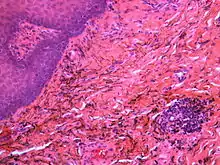

هو تشخيص سريري [4]:138 حيث يمكن تمييز الوشم الملغمي عن غيره من أسباب التصبغ الموضعي الفموي؛ لأنه لا يتغير بشكل كبير في الحجم أو اللون [4]:138، وبالرغم من ذلك قد يبدو لنا أنه يزداد بالحجم ببطء لعدة أشهر بعد الغرس الأولي للجزيئات المعدنية [2][6]:183 وفي بعض حالات الوشم الملغمي تظهر معتمة في الصورالإشعاعية (أي أنها تظهر على الأشعة السينية) [4]:138 ، والبعض الآخر ليس له ميزات التصوير الإشعاعي لأن جسيمات الملغم صغيرة جدا بالرغم أنه سريريا قد يظهر التصبغ أكبر من ذلك بكثير.[2] وإذا لزم الأمر، يمكن تأكيد التشخيص عن طريق أخذ خزعة التي تستثني الشامات والأورام الميلانينية[4]:138 إذا تم استئصال الخزعة وتظهر الأنسجة كما يلي:[2]

• فتات ملون من المعدن داخل النسيج الضام .

• تلون ألياف الريتيكولين بأملاح الفضة.

• حبيبات كبيرة غامقة صلبة متناثرة ذات اللون البني الداكن أو الأسود.

• جزيئات كبيرة قد تكون محاطة بأنسجة ليفية ملتهبة بشكل مزمن.

• جسيمات صغيرة محاطة بأنسجة ذات التهاب حاد بشكل واضح، والتي قد تكون أورام حميدة أو خليط من الخلايا الليمفاوية وخلايا البلازما.